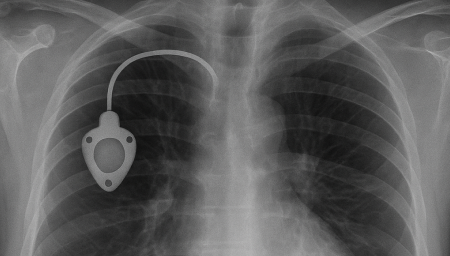

Chemoport는 항암제처럼 자극이 강한 약물을 안전하고 안정적으로 투여하기 위해

흉부 피부 아래에 이식하는 중심정맥 사용 포트입니다.

Chemoport는 항암제처럼 자극이 강한 약물을 안전하고 안정적으로 투여하기 위해 흉부 피부 아래에 이식하는 중심정맥 사용 포트입니다. 팔 혈관이 약하거나 반복 주사로 인한 통증이 걱정되는 환자에게 도움을 줄 수 있으며, 장기간 치료가 필요한 경우 편안하게 항암 치료를 지속할 수 있도록 설계되어 있습니다.

항암관(Chemoport)삽입 과정

국소마취 후 작은 절개를 시행 (보통 쇄골 아래 약 2~3cm 정도 절개)

정맥에 카테터 삽입 후 포트와 연결

방사선으로 카테터 위치 확인

피부 봉합 후 소독 드레싱